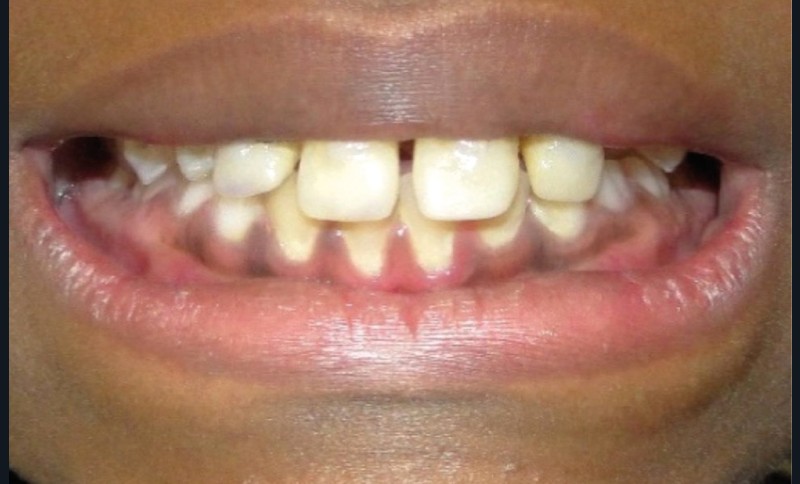

Lors de la première consultation, des photographies exo-buccales (fig. 2a, b) et endo-buccales (fig. 3) ont été réalisées ainsi que des empreintes optiques dans le but d’obtenir des modèles d’étude numériques.